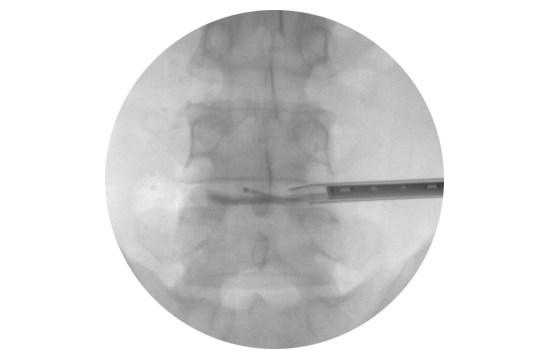

천골 열공 부위 위치를 잡은 후 먼저 부분 마취를 하고 5mm 정도 절개합니다.

절개부위를 통해 천미인대를 뚫고 투관침을 삽입하여 형광투시경 영상을 보며 진입시킨 후 이를 통해 카테터를 집어 넣습니다.

형광투시경과 내시경 이미지를 보면서 카테터를 추간판 수핵탈출 부위까지 진입시킵니다.